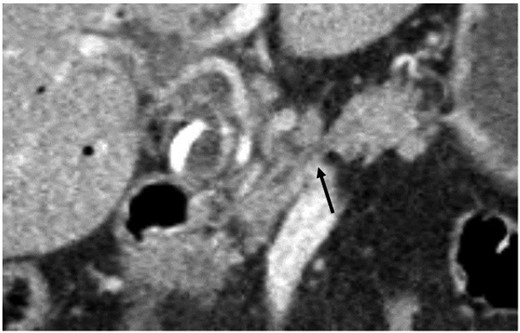

A 78-year-old woman with metabolic syndrome and chronic obstructive pulmonary disease developed obstructive jaundice and underwent endoscopic biliary stenting and papillotomy for suspected periampullar carcinoma (double-pigtail endoprothesis, 10 Fr./7 cm). Histology revealed a moderately differentiated bile duct carcinoma. Cytopathology showed a class V PAP stain with adenocarcinoma cells. The abdominal computed tomography displayed an inhomogenous hypodense tumor in the pancreatic head of 2 cm diameter with no signs of metastatic spread. The proximal part of the pancreatic corpus seemed to be atrophic (see Fig. 1). Endosonography demonstrated a tumor of the ampulla of Vater with a size of 20 × 23 mm and infiltration of the duodenal wall (at least uT2uN1).

Coronary abdominal CT scan: missing pancreatic isthmus with isolated pancreatic duct (arrow).